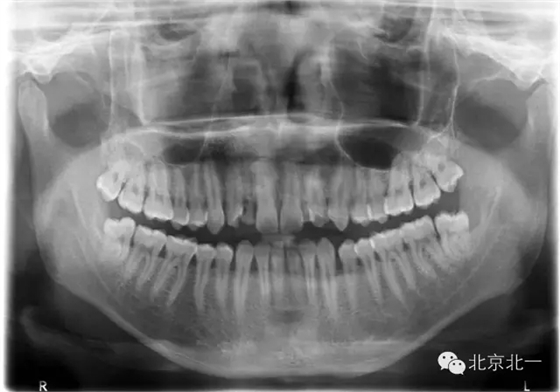

手術前拍CBCT及全景片、右上中切牙根尖高密度印象。

手術后拍全景片,順便把滯留乳牙拔除了。